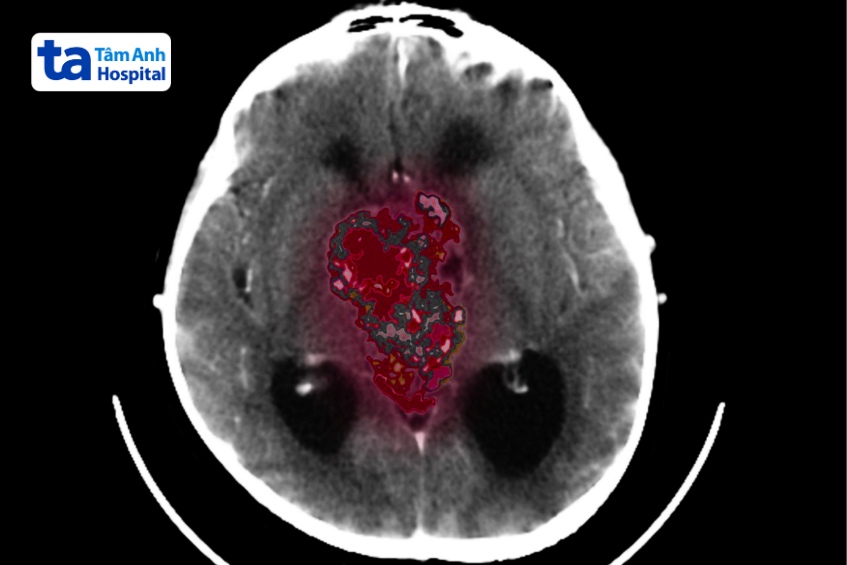

Chẩn đoán hình ảnh: Chụp cộng hưởng từ (MRI) có tiêm thuốc cản quang để phát hiện u màng não thất, chụp cắt lớp vi tính (CT Scan) được sử dụng khi không thể thực hiện MRI, giúp phát hiện vôi hóa hoặc tình trạng tắc nghẽn dòng chảy dịch não tủy gây não úng thủy.

Xét nghiệm hình ảnh chẩn đoán bệnh u màng não thất